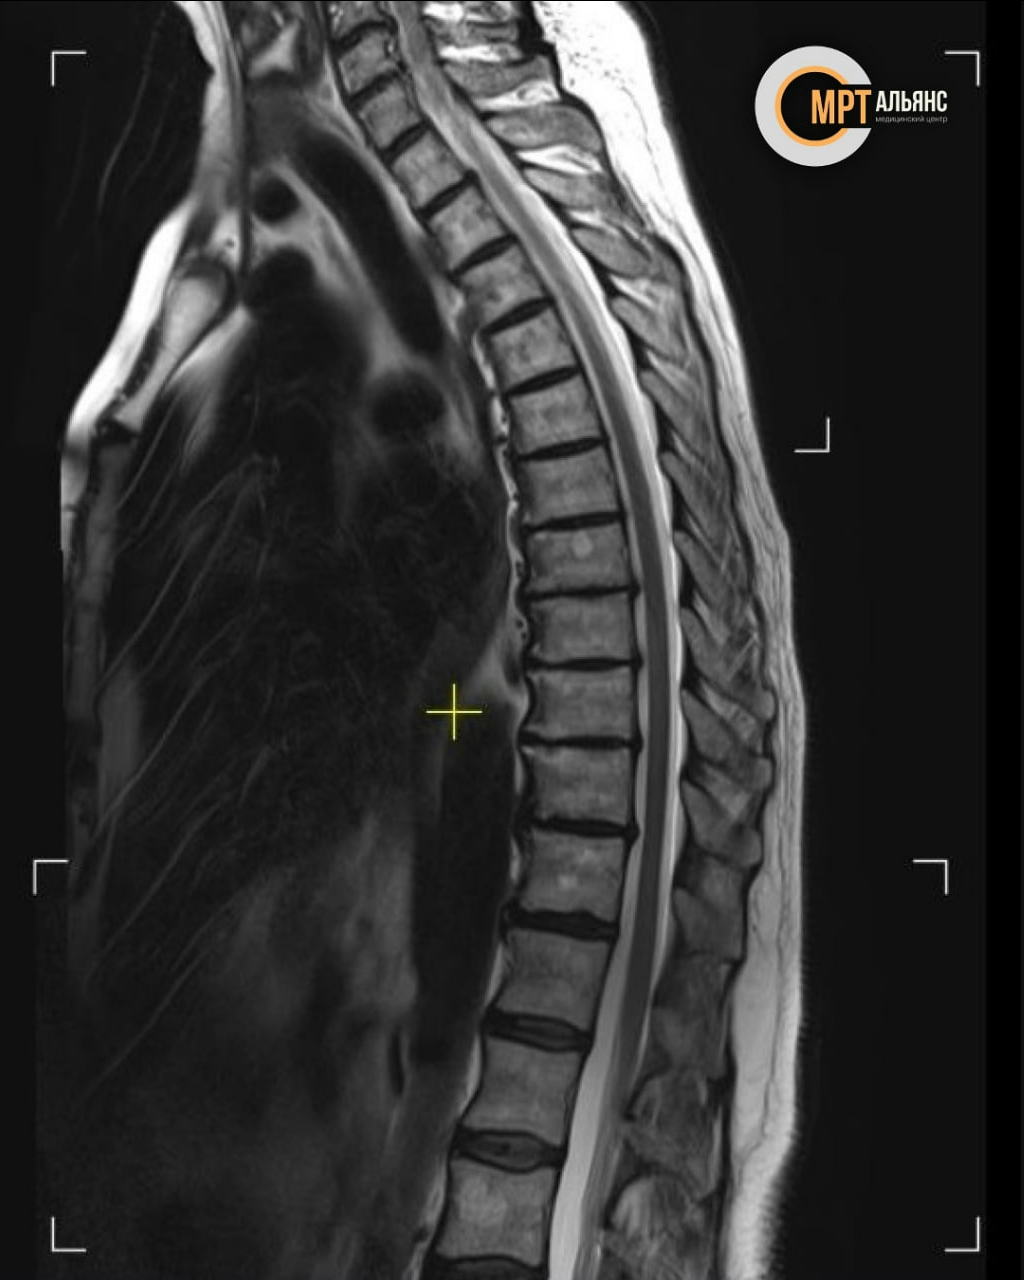

МРТ позвоночника выявляет проблемы, которые не видны другими методами:

✅ Остеохондроз

✅ Межпозвонковые грыжи и протрузии

✅ Опухоли и гемангиомы

✅ Спондилоартроз

✅ Компрессионные переломы

Обследование показывает состояние позвонков, дисков, нервов, сосудов и спинного мозга с высокой детализацией